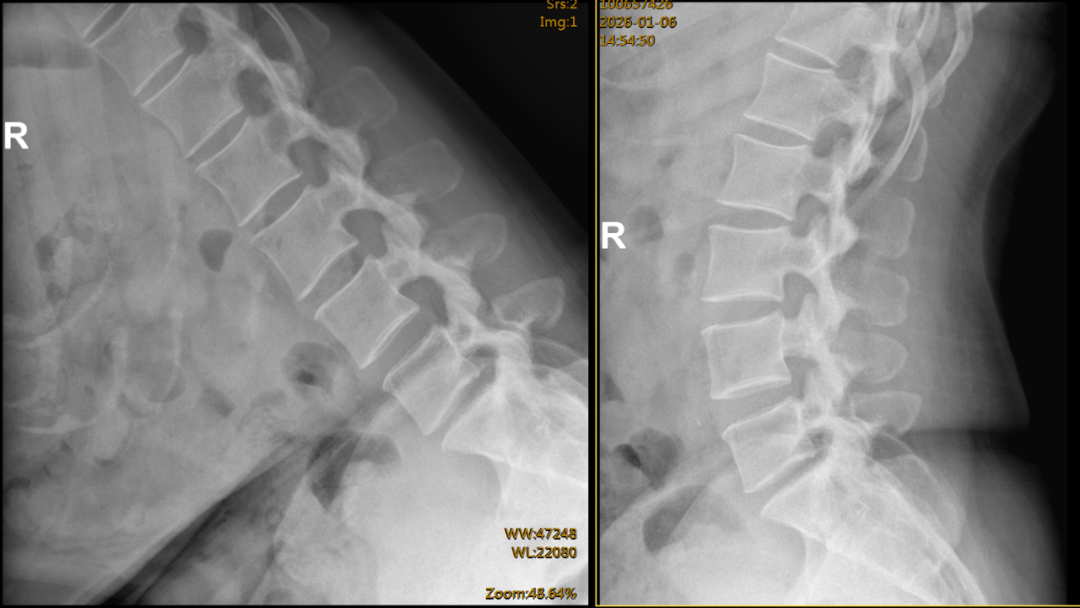

术前腰椎间盘CT示腰5-骶1椎间盘左侧突出,并伴有部分骨化